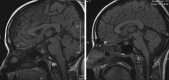

Background: Colloid cysts are usually located at the rostral part of the third ventricle in proximity to the foramina of Monro. Some third ventricular colloid cysts, however, attain large sizes, reach a very high distance above the roof of the third ventricle, and pose some challenges during endoscopic excision. These features led to the speculation that for such a pattern of growth to take place, the points of origin of these cysts should be at areas away from the foramina of Monro at which some anatomical "windows" exist that are devoid of compact, closely apposed forniceal structures.

Results: Colloid cysts may grow vertically up past the roof of the third ventricle through anatomical windows devoid of the mechanical restraint of the forniceal structures.

Conclusion: Some anatomical variations of the forniceal structures may allow unusually large sizes and superior vector of growth of a retro- or post-foraminal colloid cyst. Careful preoperative planning and knowledge of the pertinent pathoanatomy of these cysts before endoscopic excision is very important to avoid complications.